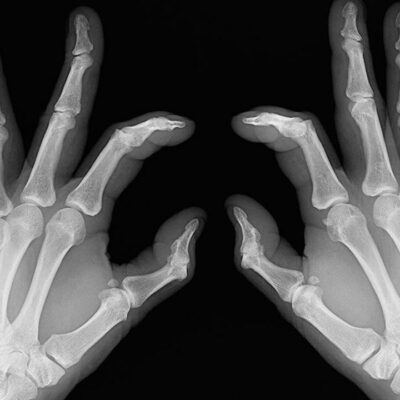

Rheumatoid arthritis causes chronic inflammation of joints, which results in joint pains, inflammation and bone deformation. It usually starts slowly with pain in some parts of the body that can come and go in the beginning and then spread within weeks or months. It is better in this day and age to always be aware of your health problems and not to ignore slightest of joint pains.